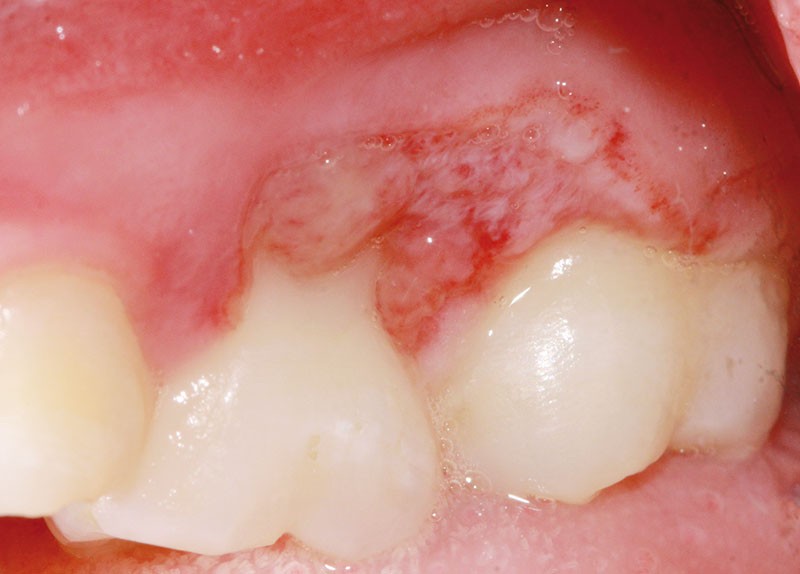

L’examen clinique révèle la présence d’une ulcération végétante, d’environ 1 cm de diamètre, localisée sur les gencives marginale, papillaire et attachée en vestibulaire de 55 et 16, associée à une récession parodontale pour 55. L’ulcération est bien délimitée, indolore et non hémorragique spontanément. Les dents présentent une mobilité physiologique et il n’existe pas d’adénopathie.